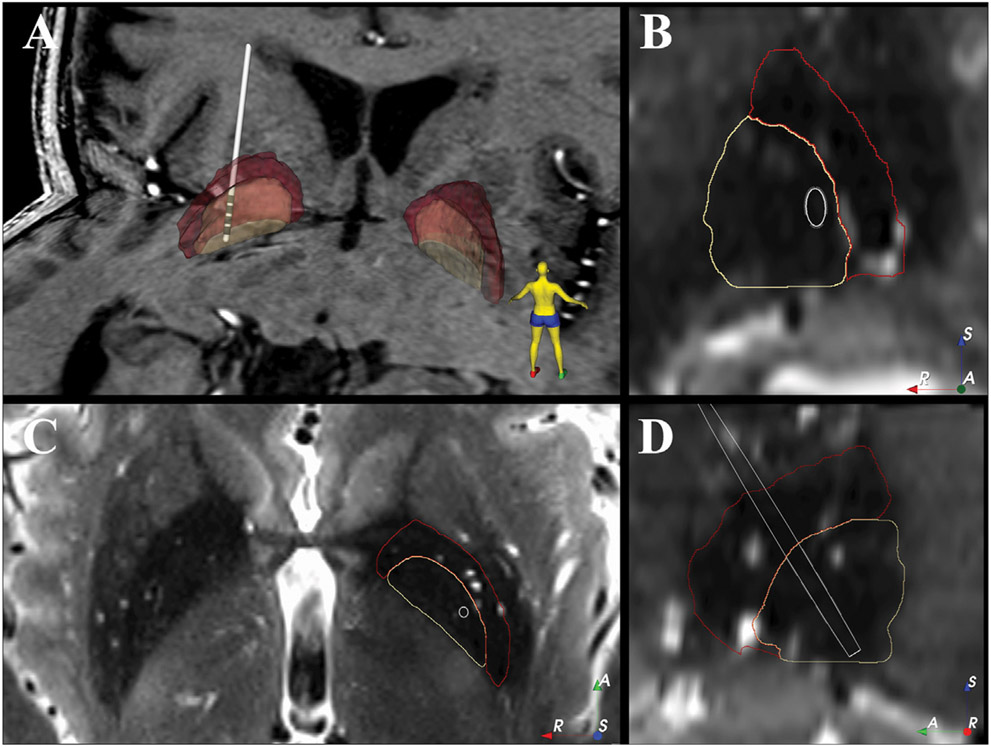

Freezing of gait (FOG) is a particularly debilitating symptom of Parkinson's disease (PD) and is often refractory to treatment. A striking feature of FOG is that external sensory cues can be used to overcome freezing and improve gait. Local field potentials (LFPs) recorded from the subthalamic nucleus (STN) and globus pallidus (GP) show that beta-band power modulates with gait phase. In the STN, beta-band oscillations are modulated by external cues, but it is unknown if this relationship holds in the globus pallidus (GP). Here we report LFP data recorded from the left GP, using a Medtronic PC + S device, in a 68-year-old man with PD and FOG during treadmill walking. A "stepping stone" task was used during which stepping was cued using visual targets of constant color or targets that unpredictably changed color, requiring a step length adjustment. Gait performance was quantified using measures of treadmill ground reaction forces and center of pressure and body kinematics from video monitoring. Beta-band power (12-30 Hz) and number of freezing episodes were measured. Cues which unpredictably changed color improved FOG more than conventional cues and were associated with greater modulation of beta-band power in phase with gait. This preliminary finding suggests that cueing-induced improvement of FOG may relate to beta-band modulation.